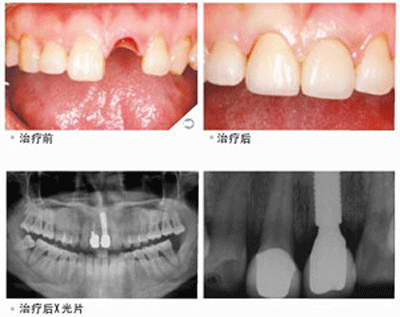

3、种植牙:种植牙是牙缺失修复方式中的佼佼者,它无需磨牙,体积小,更坚固,更美观,更舒适,一致以来都被国内外口腔医生认为是人类的第三幅牙齿,只是制作成本高,因此价格比较昂贵。